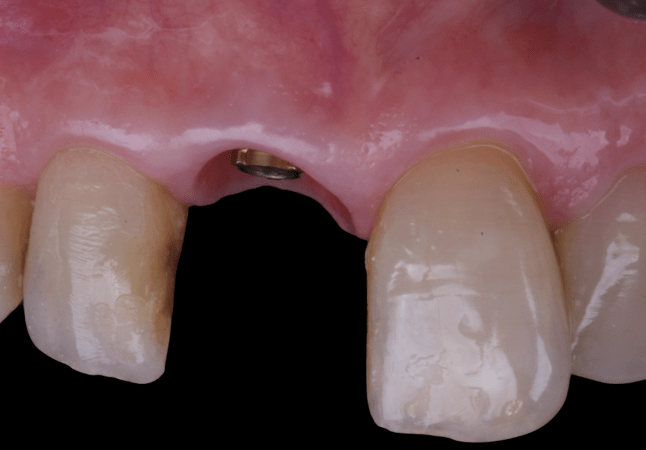

On the same day as the surgery, an immediate-load provisional crown was delivered. This restoration was fabricated in acrylic resin and screw-retained on the implant, following the “one abutment one time” principle. The provisional crown was carefully adjusted to avoid occlusal loading while supporting the peri-implant soft tissue architecture during the healing phase.

The provisional not only satisfied the patient’s functional and esthetic demands but also played a key role in shaping the emergence profile and conditioning the gingival margin. By providing a provisional solution immediately, the patient was able to leave the clinic with a natural-looking smile, avoiding any psychological or social impact associated with tooth loss in the anterior maxilla.